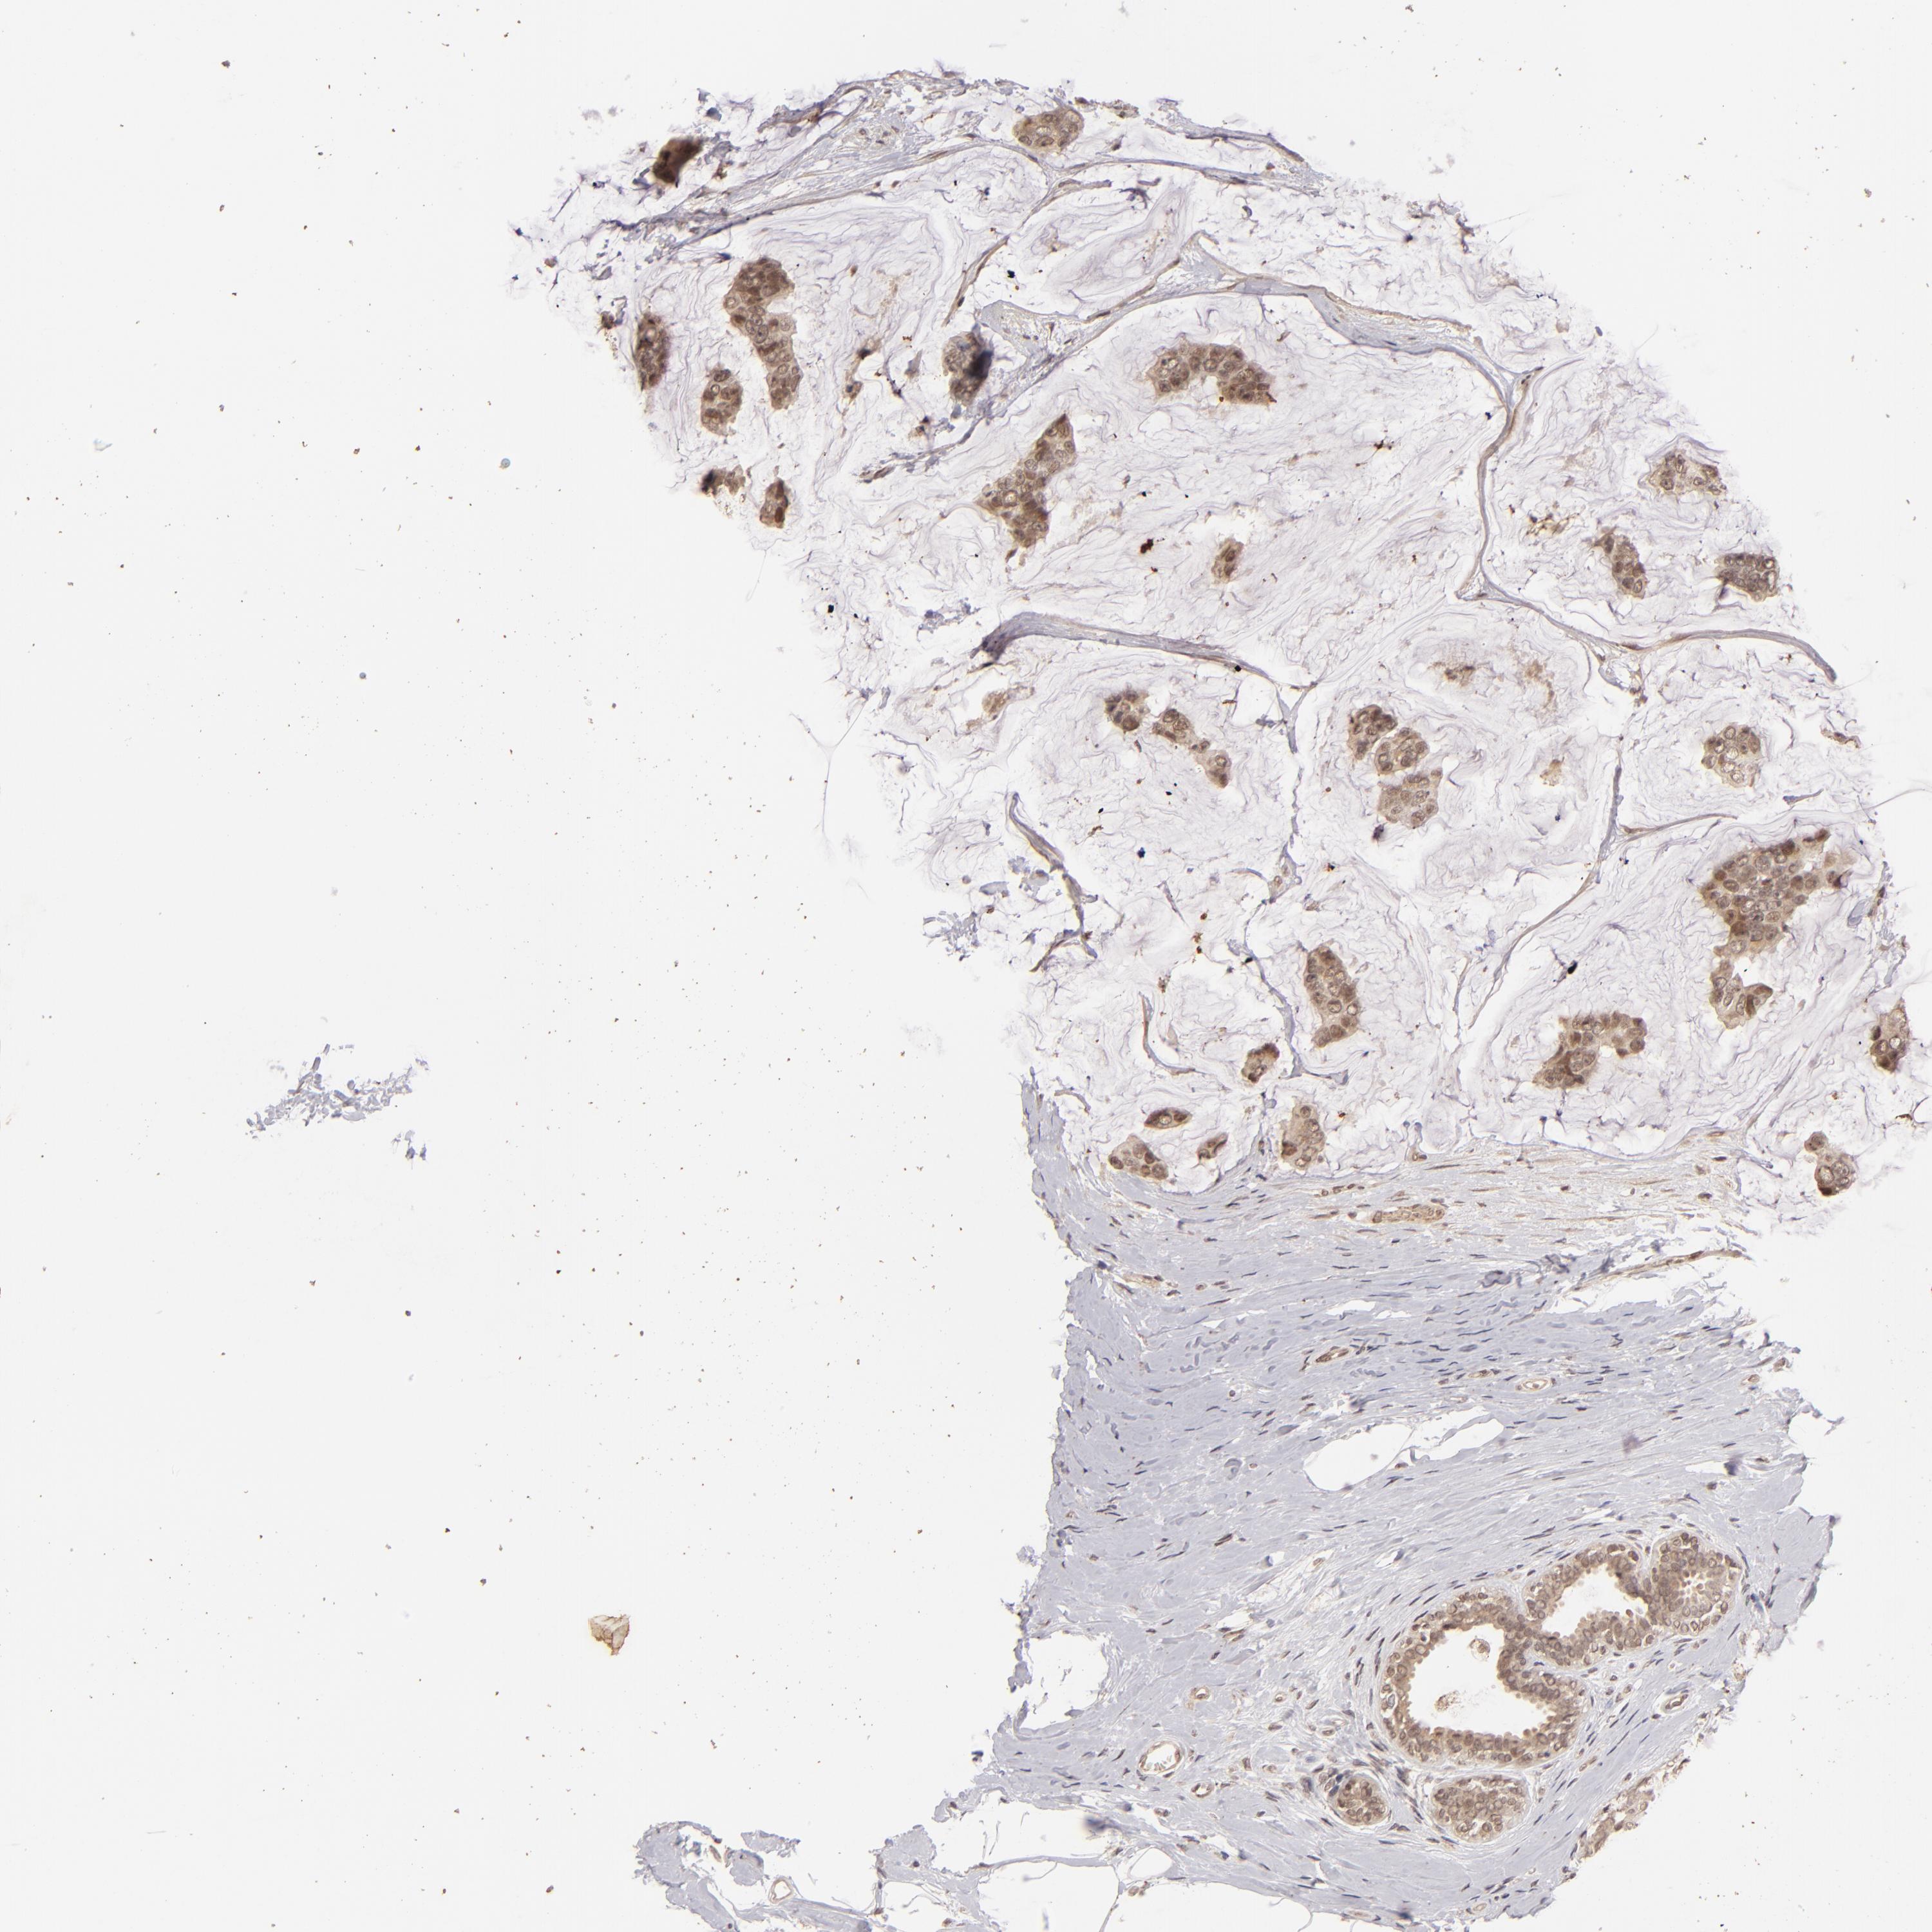

CANCER BREAST CANCER Show tissue menu

BRCA TCGA BRCA VALIDATION PROTEIN EXPRESSION

ANTIBODIES

AND

VALIDATION